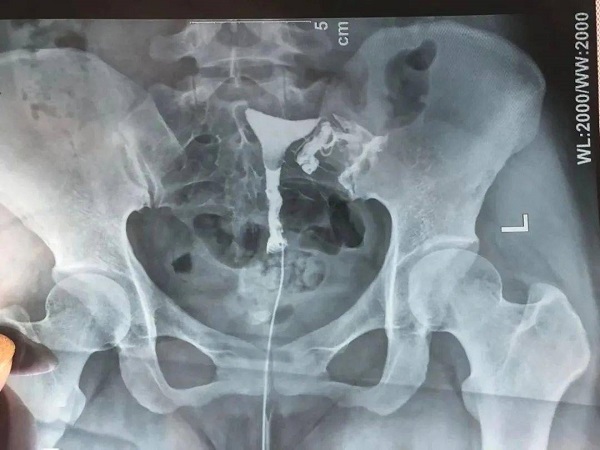

导丝介入疏通输卵管也被称之为输卵管阻塞再通术,主要就是在影响设备的全程引导下,通过女性的阴道达到子宫然后到达输卵管,找到不通畅的输卵管,就能够明确输卵管出现病变的原因,然后就可以达到诊断和治疗的双重目的。这种介入治疗的过程是比较简单的,并且时间也比较短,一般10分钟就可以疏通输卵管,疏通率可以达到90%,患者可以了解一下。

1术前检查:在女性月经后一周就需要去医院进行一些常规检查和妇科检查,如果检查没有炎症的话,那么就可以及时安排手术时间了,但是如果身体存在炎症的话,就需要治疗好之后在进行手术;2术前准备:手术前需要进行常规的消毒工作,将女性的阴道、外阴进行消毒,以免在手术过程中出现感染,然后将女性的宫颈口使用鸭嘴钳扩张开;3导丝介入:将宫腔镜推进女性的宫底,然后找到输卵管的位置,将导管在宫腔镜的引导下插入女性的输卵管,然后想输卵管中注入药物查看情况;4疏通:注入药物后如果就需要将导丝送入输卵管中然后进行通液,直到输卵管不再出现反流现象即可。